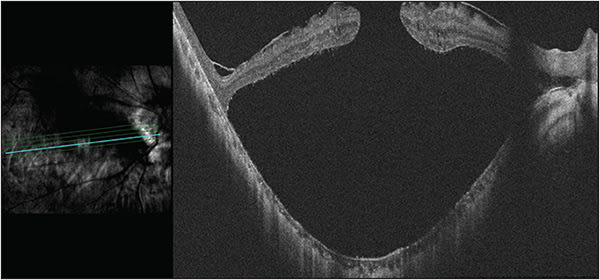

Tractional forces elongating the eye perpendicularly to the retinal plane can result in foveoschisis with RD without breaks. Similar to MHRDs, FSRDs may be treated with PPV with or without ILM peeling34 and/or macular buckling (Figure 3). Again, cases with extreme myopia (>30 mm axial length) may be most likely to benefit from the inclusion of a macular buckle.

Unique to FSRDs, a “fovea-sparing” technique has been developed for the ILM peel to avoid the induction of FTMHs. The inflexibility of the ILM while the eye elongates is thought to contribute to the onset of foveoschisis, which is why ILM peeling is commonly performed along with PPV in such cases. Although ILM peeling may relieve tractional forces perpendicular to the retinal plane, it also increases the risk of postoperative development of a FTMH in high myopes. Therefore, Shimada et al developed the technique of fovea-sparing ILM peel to mitigate this risk.35 The ILM peel is limited to the parafovea and perifovea, eliminating tangential traction adjacent the fovea. Using this technique, Shimada et al found that 0 of 15 eyes developed FTMH as compared to 5 of 30 eyes in the complete ILM peel group.35